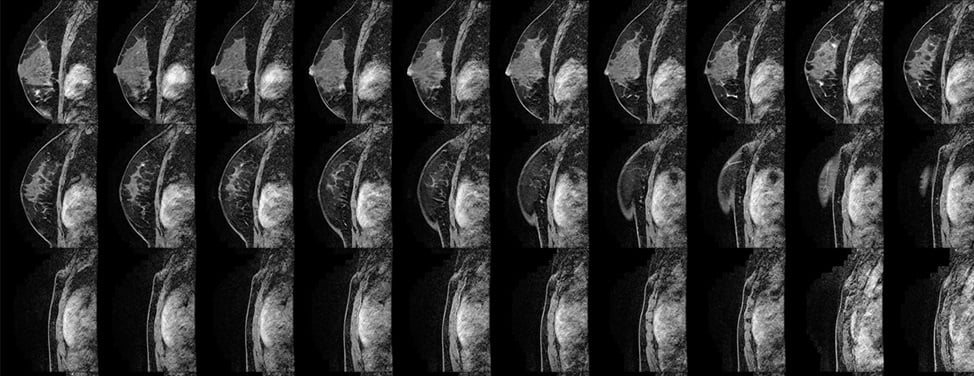

The goal of screening examinations for early breast cancer detection is to find cancers before they start to cause symptoms. Breast cancers that are detected because they cause symptoms tend to be relatively larger and likely to have spread beyond the breast. In contrast, breast cancers found during screening examinations are more likely to be small and still confined to the breast.

The American Cancer Society believes the use of mammography, clinical breast examination and breast self-examination offers women the best opportunity for reducing the breast cancer death rate through early detection. This combined approach is clearly better than any one examination. The American Cancer Society does not recommend relying solely on any of these methods.

- Have a mammogram every year